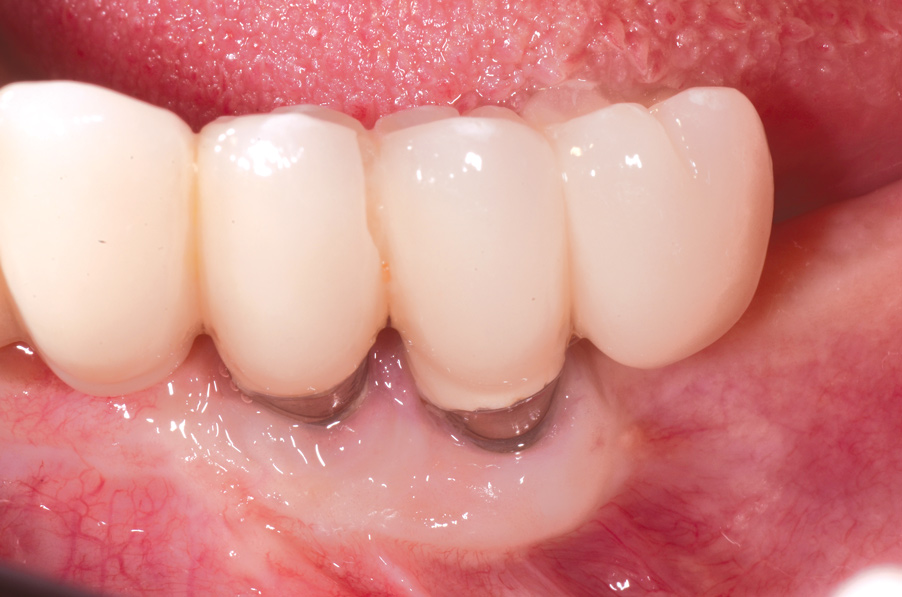

Fig 1. Clinical view of severe gingival inflammation with possible early bone loss present around the implant at the site of the maxillary left first molar. The two premolar implants had mucogingival deformities.

Figure 1